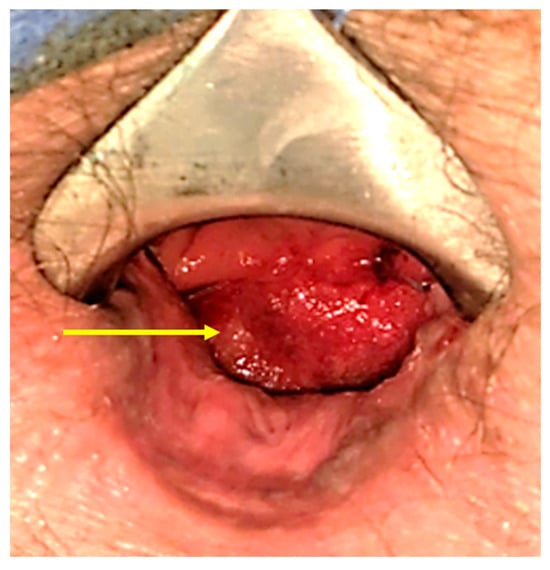

After the reversal, the patient, who was on Apixaban for a history of provoked pulmonary embolism, developed rectal bleeding that required a blood transfusion. Examination under anesthesia revealed an ulcer with granulation tissue on the anterolateral rectal wall as the source of bleeding. Hemostasis was achieved with bipolar cautery and sutures. Subsequent sigmoidoscopy showed a deep ulcer with granulation tissue but no active bleeding (Figure 4C).

The patient underwent multiple sessions of hyperbaric oxygen therapy (HBOT). A follow-up sigmoidoscopy three months later revealed that the ulcer had healed, although a small sinus opening was still suspected (Figure 4D). The patient has finished the HBOT treatments and is currently receiving physical therapy with biofeedback to support recovery.

Figure 3. An examination under anesthesia, conducted after six sessions of intraluminal vacuum therapy, revealed the closure of the anterior–lateral abscess cavity with the presence of granulation tissue (yellow arrow).